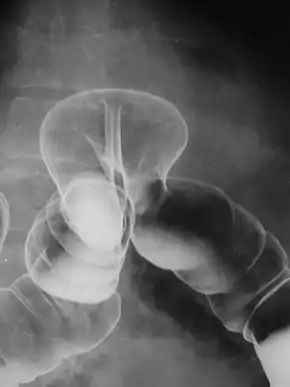

A hiatus hernia is a particular variant of this type, in which the normal passageway through which the esophagus meets the stomach (esophageal hiatus) serves as a functional "defect", allowing part of the stomach to (periodically) "herniate" into the chest. Hiatus hernias may be either "sliding", in which the gastroesophageal junction itself slides through the defect into the chest, or non-sliding (also known as para-esophageal), in which case the junction remains fixed while another portion of the stomach moves up through the defect. Non-sliding or para-esophageal hernias can be dangerous as they may allow the stomach to rotate and obstruct. Repair is usually advised.